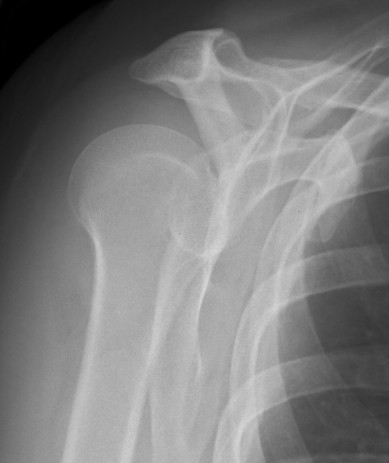

AP in plane of scapula

Grashey

- angle 45o lateral

- allows estimation of glenohumeral space